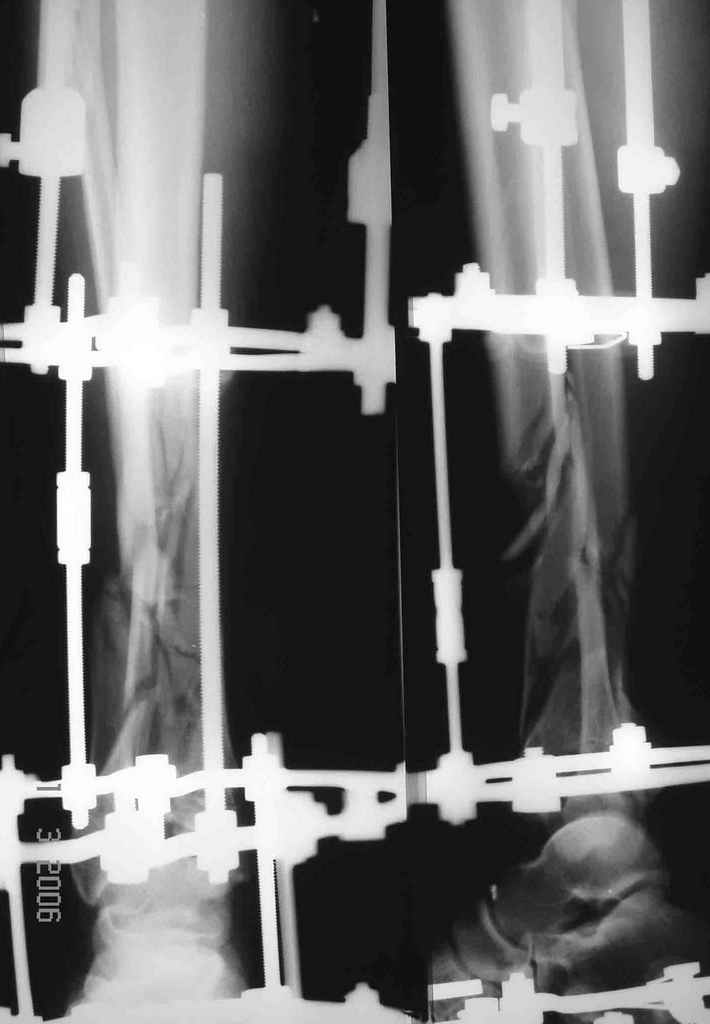

Вот что получилось

7.jpg

27KB (28411 bytes)

А была ли необходимость менять аппарат на такую пластину? Выигрываем в возможности более ранней разработки голеностопного сустава?

Пластинка красивая. Чуть только спереди назад идет, не сосем по оси большеберцовой кости. А там не маловато фиксаторов собственно в дистальном суставном конце кости? А вправляли его как? Как будто или осталось запрокидывание кзади или недонизведен передний край. Но с учетом исходного тяжелейшего повреждения - все равно здорово.